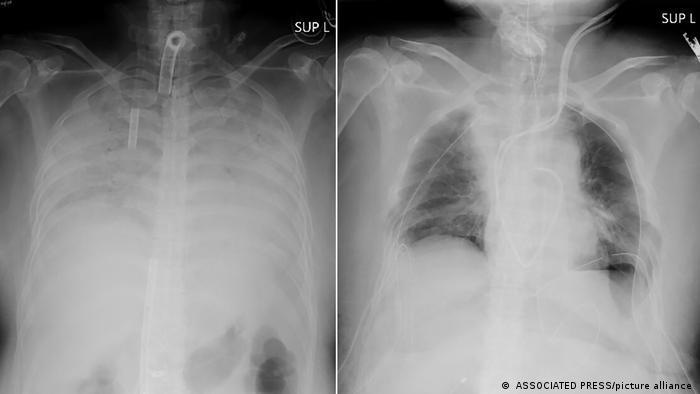

اولین پیوند ریه جهان از اهداکننده زنده به بیمار مبتلا به کووید ۱۹

بیمارستان وابسته به دانشگاه کیوتو از جراحی موفقیتآمیز پیوند ریه از اهداکنندگان زنده به زنی مبتلا به بیماری کووید ۱۹ خبر داد.

به گزارش سیانان، این بیمارستان اعلام کرد، این زن که آسیب ریوی شدیدی دیده بود هفته گذشته توسط یک تیم پزشکی ۳۰ نفره تحت عملی ۱۱ ساعته قرار گرفت و جانش بر اثر اهدای قسمتهایی از ریه همسر و پسرش نجات یافت.

بیماری کووید ۱۹ که بر اثر آلودگی به ویروس کرونا به وجود میآید در برخی بیماران بهشدت به ریهها آسیب میرساند.

بیمارانی از سراسر جهان، از جمله آمریکا از پیوند ریه برای نجات ریههای خود استفاده کردهاند.اما به گفته بیمارستان کیوتو، این اولین بار است که بافت ریه از اهداکنندهای زنده به بیمار مبتلا به کووید ۱۹ اهدا میشود.

دکتر هیروشی دیت، جراح قفسه سینه در این بیمارستان که هدایت این عمل جراحی را بر عهده داشت گفت، این روش درمانی بیمارانی که ریهشان آسیب شدیدی از بیماری کووید ۱۹ دیده را امیدوار کرده است.

او در کنفرانسی خبری در پنجشنبه گذشته ۸ آوریل یادآور شد: «ما نشان دادیم که حالا گزینهای برای پیوند ریه [از اهداکنندگان زنده] داریم.»

به گفته بیمارستان کیوتو، این بیمار که زنی است از منطقه غربی کانسای ژاپن، در اواخر سال گذشته به کووید ۱۹ مبتلا شد و ماهها برای ادامه زندگی به دستگاه تنفس مصنوعی وصل بود.

همسر و پسر او بعد از آن که مشخص شد بیمار که ریههایش کارایی لازم را نداشت برای ادامه زندگی به پیوند ریه محتاج است، پیشنهاد اهدای قسمتی از ریه خود را مطرح کردند.

در بیانیه این بیمارستان آمده که پیوند از بیمار دچار مرگ مغزی هنوز نادر است و اهداکننده زنده گزینه بهتری محسوب میشوند.

وضعیت همسر و پسر او بعد از اهدا پایدار اعلام شده و پیشبینی میشود، این زن نیز که اکنون در مراقبتهای ویژه به سر میبرد حدود دو ماه دیگر از بیمارستان مرخص شود.